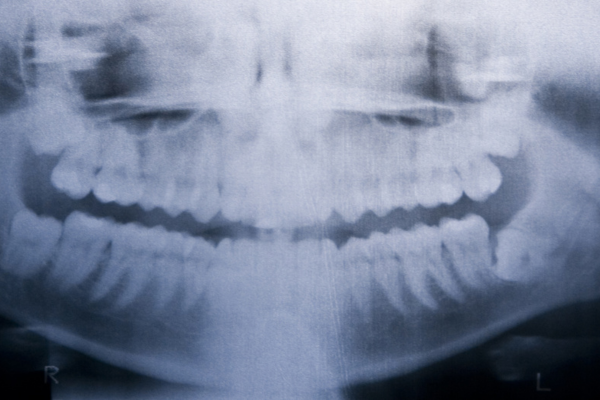

中京病院 歯科口腔外科は、名古屋市中区に位置する総合病院内の専門診療科で、特に口唇口蓋裂や口腔がんをはじめとした高度な外科治療に力を入れています。医療連携を重視した診療体制のもと、小児期から成人に至るまで長期的な治療計画を立て、形成外科や耳鼻科、麻酔科など多職種と協働しながら治療を進めています。

同科では、口唇口蓋裂の治療として、出生直後の哺乳支援から形成術、矯正治療、言語療法まで一貫した対応が可能であり、成長に伴う顔面の発育を見守りながら丁寧にフォローを行います。また、口腔がんに対しては早期発見と根治的な外科治療を基本とし、進行がんには高精度放射線治療(IMRT)や化学療法も取り入れた集学的治療が行われています。

中京病院 歯科口腔外科では、専門の歯科医師による高い技術と豊富な臨床経験に加え、歯科衛生士による口腔ケアも受けられる環境が整っており、顎変形症や顎関節症、埋伏歯の外科処置、インプラント治療にも対応。地域の開業医とも連携し、必要に応じて症例検討を行うなど、地域医療の中核としても重要な役割を担っています。